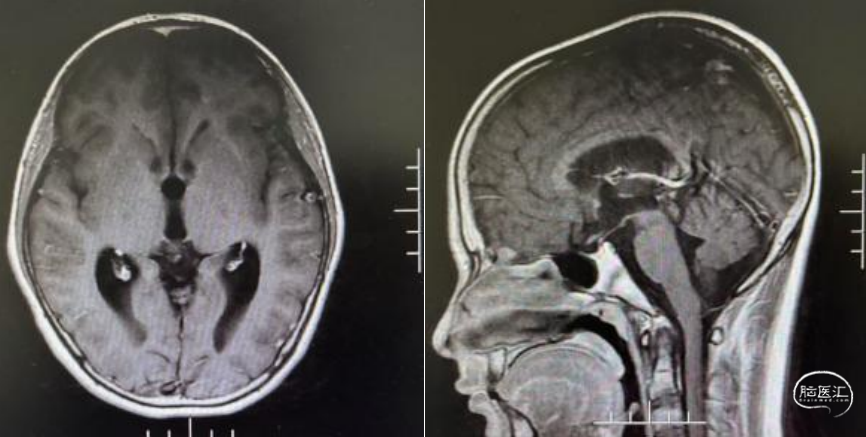

头部CT显示:左侧基底节区囊实性占位性病变,大小约40*36mm,内有多发钙化,低密度区CT值约12HU,临近脑实质密度减低,左侧脑室,邻近中线结构右移。

头部MRI显示:左侧基底节区囊实性肿块,内见实性成分及分隔,呈稍长T1稍长T2信号灶,FLARE呈高信号,大小约47*39*40mm,增强后实性成分及分隔明显强化。右侧侧脑室受压,周围脑实质可见条片状稍长T2水肿带,中线右移。

经纵裂胼胝体入路全切除病变。右侧肢体肌力4级。

病理检查:(左侧基底节)混合性生殖细胞肿瘤(50%生殖细胞瘤+50%胚胎性肿瘤)。免疫组化:CK-Pan(+),CD117(+),D2-40(+),Oct(+),AFP(部分+),PLAP(部分+),CD30(+),HCG(-),EMA(+),SALL4(+),Ki(约70%)。

术后建议辅助治疗。结疗后未见肿瘤复发,肌力已恢复至5-级。此后2年予以定期复查未见复发。

术后2年(已完成放疗化疗)